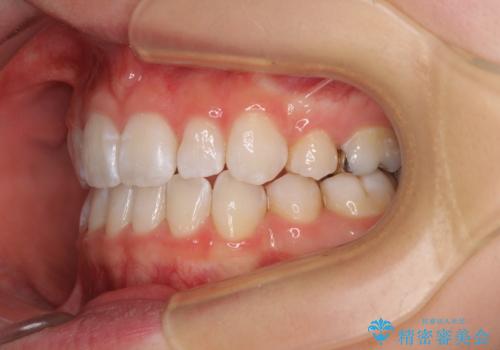

- 前歯の出っ歯と口元の閉じにくさを気にして来院された患者様です。

口元を積極的に引っ込めるために、上下左右の小臼歯4本を抜歯することとしました。

4本の歯を抜歯したことで、飛び出していた口元が引っ込み、横顔が大きく改善されました。